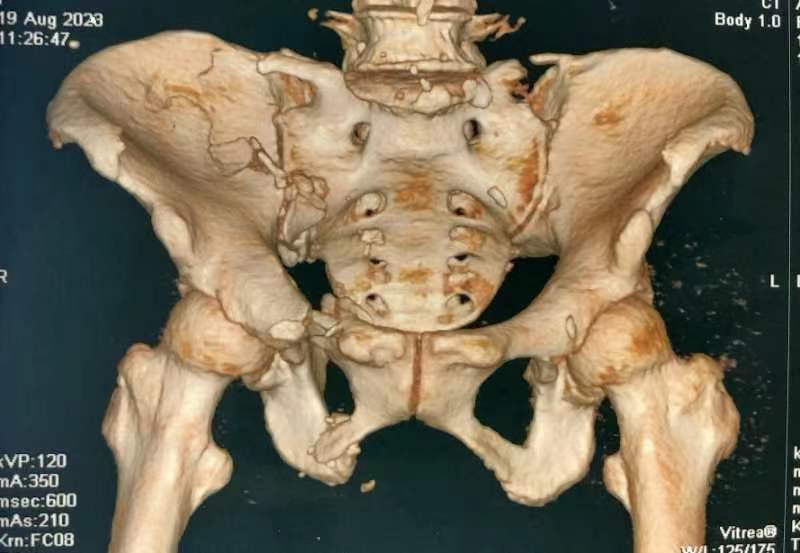

近日,乐鱼在线登录入口骨一科收治一位69岁骨折患者。患者遭遇车祸骨盆骨折、前后环损伤,造成骨盆旋转、垂直不稳定,导致翻身疼痛并且护理困难。

由于患者骨盆旋转和垂直不稳定,以及严重失血和肥胖,骨一科医疗团队进行讨论分析,决定采用微创内固定手术。8月25日成功完成手术,术后第二天患者能够在床上半靠,翻身时疼痛明显缓解,下肢功能恢复良好。